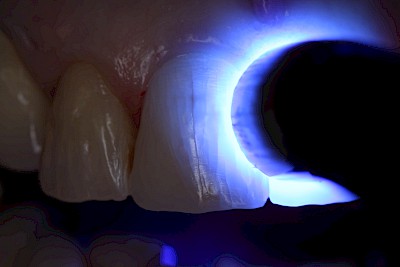

Zahn: Riss

Sprünge und Risse, meist in der Längsrichtung der Zahnkrone und häufig ausgehend vom Zahnhalsbereich, sind im Alter keine Seltenheit. In seltenen Fällen führt dies auch dazu, dass sich der Zahnnerv entzündet und auch absterben kann. In der Folge verfärbt sich der Zahn dann dunkel. Meist jedoch sind Sprünge und kleinere Risse an Zähnen über viele Jahre unauffällig und das ganze Leben über unproblematisch.

Sind Spalten an Zähnen sichtbar oder Zahnanteile beweglich, wenn man daran leicht "rüttelt", sollte umgehend der Zahnarzt kontaktiert werden.